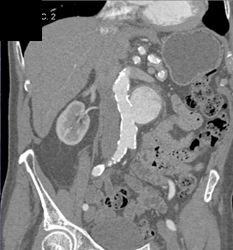

Renal Artery Aneurysm